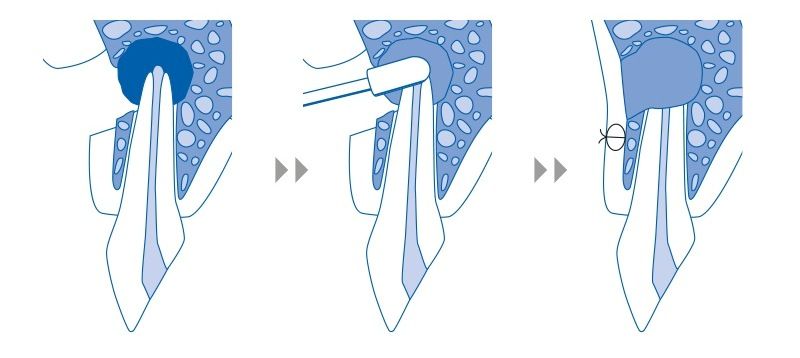

Ακροριζεκτομή είναι η χειρουργική επέμβαση, κατά την οποία αφαιρείται το άκρο της ρίζας ενός δοντιού (ακρορίζιο) που φλεγμαίνει καθώς και οι μολυσμένοι ιστοί γύρω από τη ρίζα του. Η ακροριζεκτομή εφαρμόζεται όταν ένα δόντι, που έχει ήδη θεραπευτεί με απονεύρωση, εμφανίσει φλεγμονή στο άκρο της ρίζας του. Στην περίπτωση αυτή και εφόσον ο οδοντίατρος κρίνει ότι η επανάληψη της ενδοδοντικής θεραπείας στο συγκεκριμένο δόντι δεν μπορεί να επιφέρει τα επιθυμητά αποτελέσματα, τότε η λύση επιλογής είναι η ακρορριζεκτομή. Κατά την χειρουργική αυτή επέμβαση ο οδοντίατρος προβαίνει στη μερική εκτομή της ρίζας του δοντιού. Μαζί αφαιρούνται και οι φλεγμαίνοντες παθολογικοί ιστοί γύρω από το άκρο της ρίζας. Στη συνέχεια το εναπομείναν τμήμα της ρίζας εμφράσσεται ερμητικά και συστήνεται η περιοδική παρακολούθηση του δοντιού.

Σκοπός της ακρορριζεκτομής, λοιπόν, είναι η απομάκρυνση μιας φλεγμονής που περιορίζεται στο άκρο της ρίζας ενός δοντιού και των γύρω ιστών του. Μ΄ αυτόν τον τρόπο γίνεται μία προσπάθεια διατήρησης του δοντιού στον οδοντικό φραγμό και η αποφυγή της εξαγωγής του.